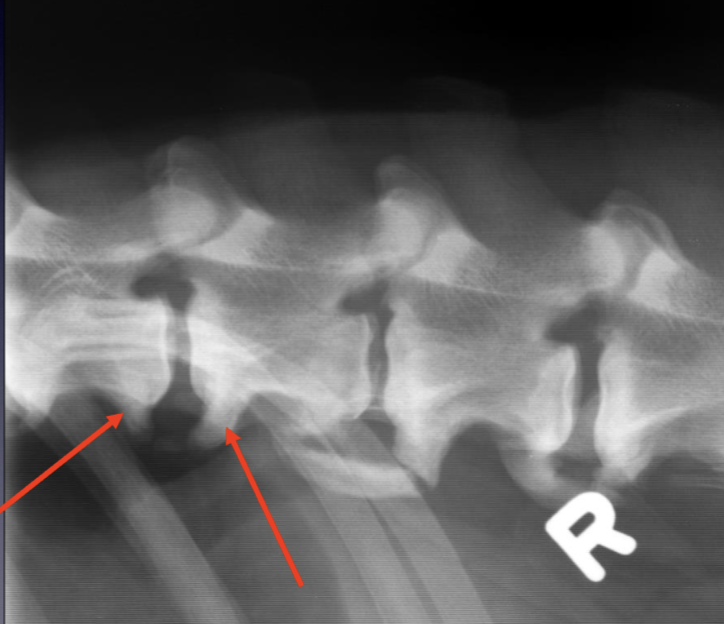

What is shown on this myelogram?

A

ventral, extradural compression at C5 to C6 and C6 to C7